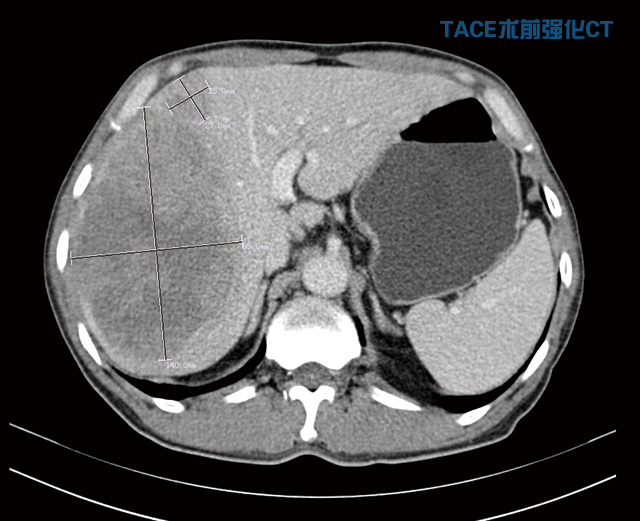

劉大爺是濰城區(qū)軍埠口鎮(zhèn)人,今年56歲。5個(gè)月前他右上腹部出現(xiàn)疼痛,在當(dāng)?shù)蒯t(yī)院檢查確診為晚期巨大肝癌,后來(lái)又去濰坊的大醫(yī)院復(fù)查,仍然是同樣的結(jié)果,醫(yī)生說(shuō)已經(jīng)沒有治療的價(jià)值,建議他回家好好享受剩下的日子。就在他絕望的時(shí)候,同村的人向他介紹了濰坊市市立醫(yī)院,說(shuō)這家醫(yī)院技術(shù)、服務(wù)都非常好,收費(fèi)也便宜。他抱著試試看的心理住進(jìn)我院普外科,經(jīng)過(guò)詳細(xì)檢查發(fā)現(xiàn),右肝巨大腫物約為14cm×12cm×9.5cm且伴仔瘤,肝硬化,左半肝變小,確診為原發(fā)性晚期巨大肝癌。

“這種情況不宜切除右半肝,因?yàn)樽蟀敫误w積小,余肝不能代償,切除后會(huì)導(dǎo)致肝功能衰竭,危及生命。必須先行介入治療,把供應(yīng)肝臟腫瘤的血管堵死‘餓死’癌細(xì)胞,使癌瘤縮小,左肝代償增大,待肝癌降期后再行手術(shù)治療,效果會(huì)比較好,也比較安全。”普外科首席專家李森主任分析說(shuō)。